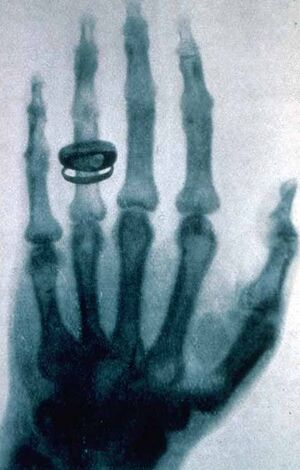

His hand was one of the first to be x-rayed, by his friend Wilhelm Röntgen.[3]